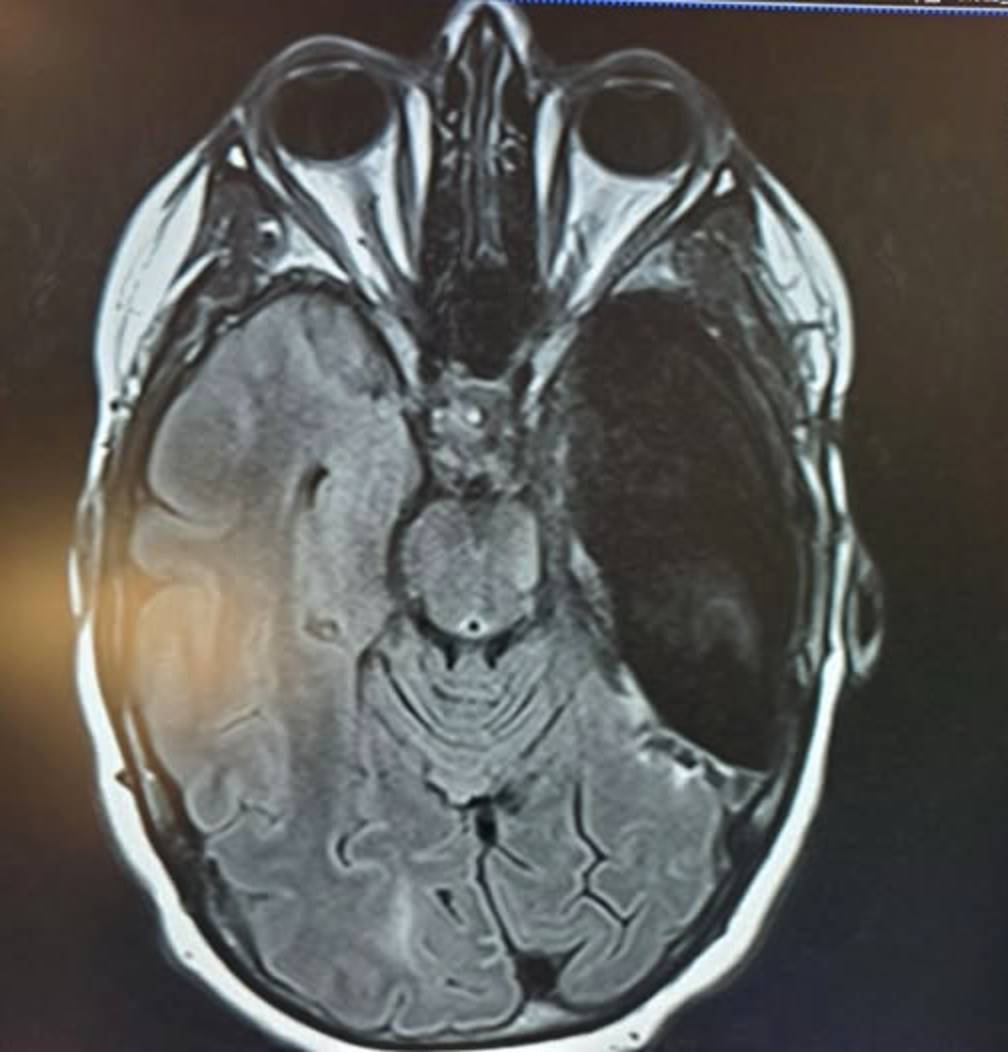

Why My Right Temporal Lobe Was Removed: Epilepsy, Mental Health, and the Road to Recovery

Right Temporal Lobectomy

At 50 I was taken to my knees by epilepsy.  I have had three invasive brain surgeries since the. 18 months ago I had my Right Temporal Lobe removed, a Lobectomy.  I am feeling much better as I recover and my brain rewires itself.  Why did I have it removed?

1. Temporal Lobe Epilepsy (TLE)

Temporal Lobe Epilepsy is the form of epilepsy most strongly associated with psychosis.

• Risk Level: Psychotic disorders affect roughly 7% to 11% of those with TLE, compared to about 3% to 5% for other seizure types.

• Location: Seizures originating in the mesial temporal lobe (deep structures like the hippocampus and amygdala) are particularly high-risk due to their role in regulating emotion and perception.